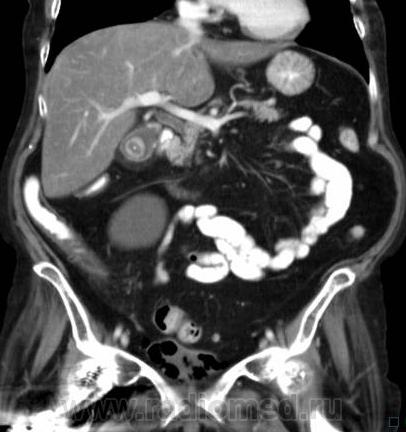

О чём могут говорить такие "газовые структуры" в области мочевого пузыря?

Наличие газа в мочевом пузыре может говорить о многом. Например стоял катетр Фолея, состояние после цистоскопии, эмфизематозный цистит, наличие фистулы.

А, чем именно, будет характеризоваться эмфизематозный цистит? При нем "пузырьки газа" локализуются в слизистой оболочке или где?

В просвете, может быть и в самой стенке. Смотрите здесь:

процесс в стенке в данном случае.

У женщины киста правой почки, подозрение на жировой гепатоз, стержень в головке и шейке правого бедра (остеосинтез). А про воздух возле/в стенке мочевого пузыря... не было ли оперативного вмешательства в малом тазу? И без аксиальных срезов явно я бы не сказала, где конкретно воздухblush...

Фик с ней с кистой... И какая разница аксиалы и короналы... Да, толстоваты срезы, эффект усреднения. Но я бы думал в сторону язвенного/гангренозного цистита (эмфизематозного цистита). Естественно, анамнез и клиника и всё встанет на свои места. На состояние после катерера не очень похоже...